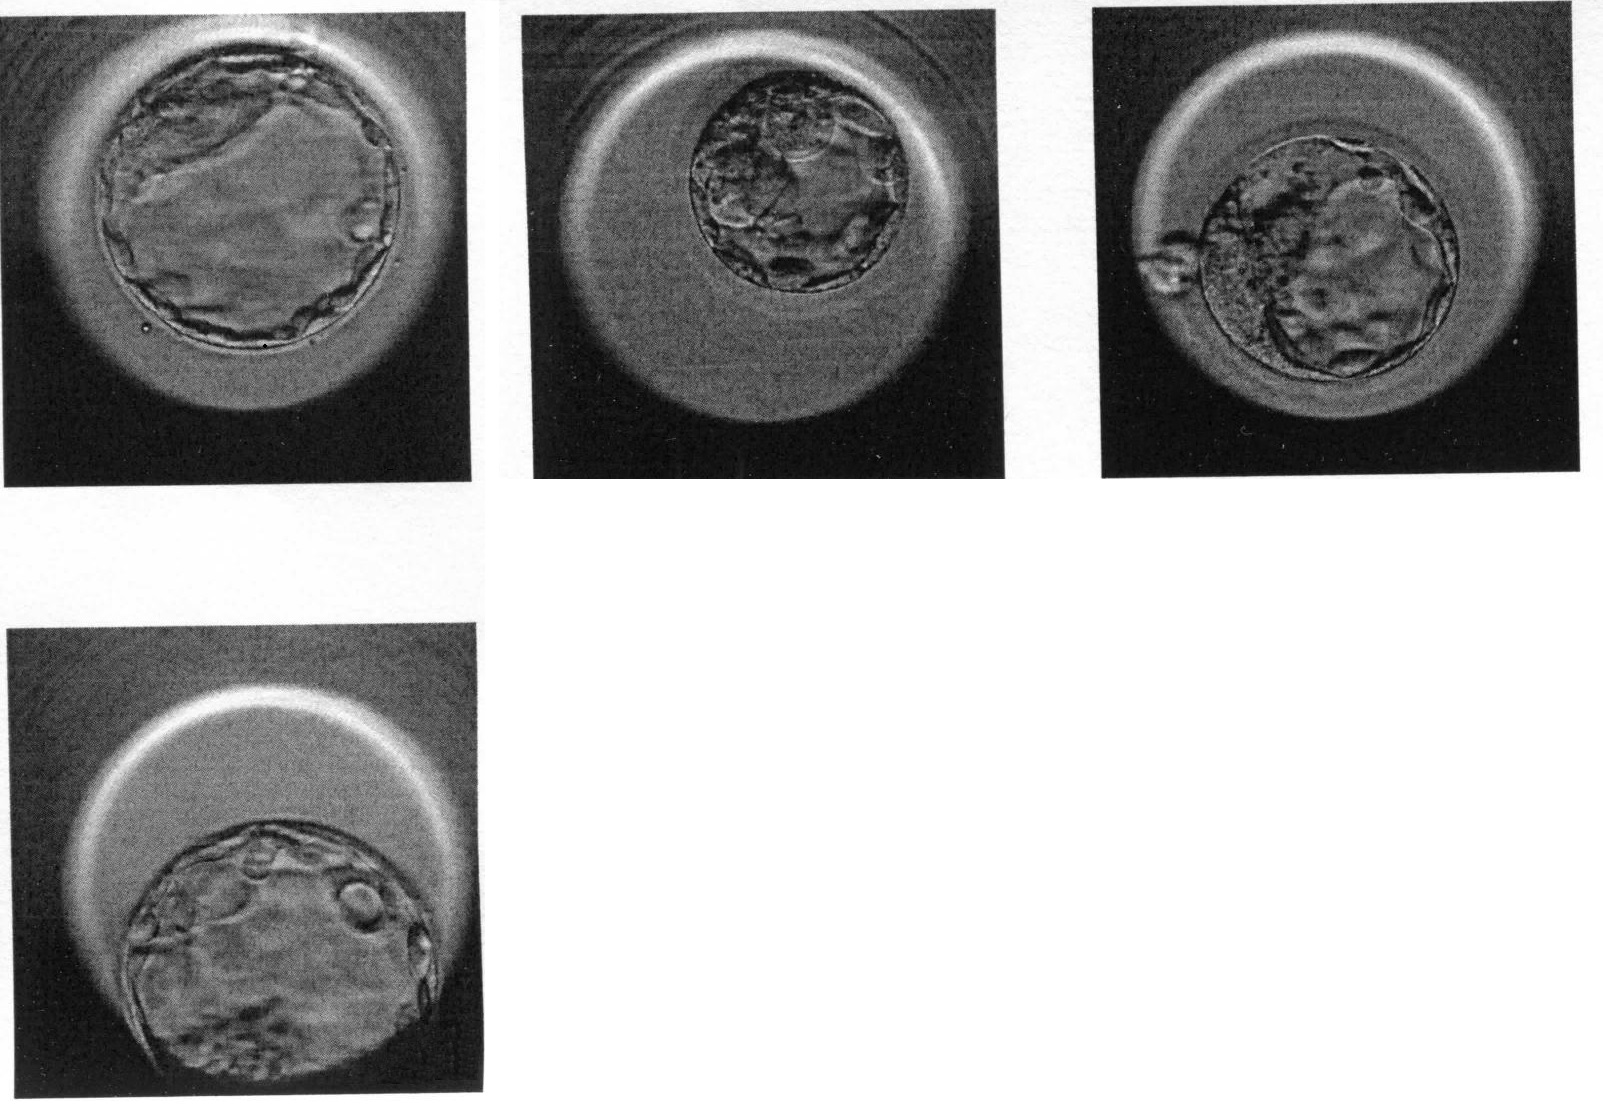

aus unsere letzten ICSI haben sich folgende 4 Blastozysten (siehe Bild, Tag 5) entwickelt.

Blasto 1 und 4 (die beiden linken) wurden mir transferiert. Leider haben wir keine genaue Angabe zu der Qualität erhalten außer dass es sehr schöne Blastozysten sind.

Die beiden anderen Blastos wurden eingefroren.

Ist die 3. Blastozyste (ganz rechts) nicht schon schlüpfend? Kann man schlüpfende Blastos überhaupt vitrifizieren?

die beiden transferierten BC sind sehr schön weit expandiert und gut strukturiert. Die obere ist etwas gleichmäßiger als die untere. (4AB + 4BB)

Die beiden BC für die Vitrifikation sind in geringerem Maß expandiert, d.h. bis zum Schlüpfen dauert es noch einen weiteren Tag. (2BB, 3BB) Die "Bläschen" sind wahrscheinlich Cumuluszellen, die auf der Oberfläche der Zona anhaften, keine Zellen der BC.

Meistens werden die BC vor dem Schlüpfen eingefroren, mit intakter Zona.